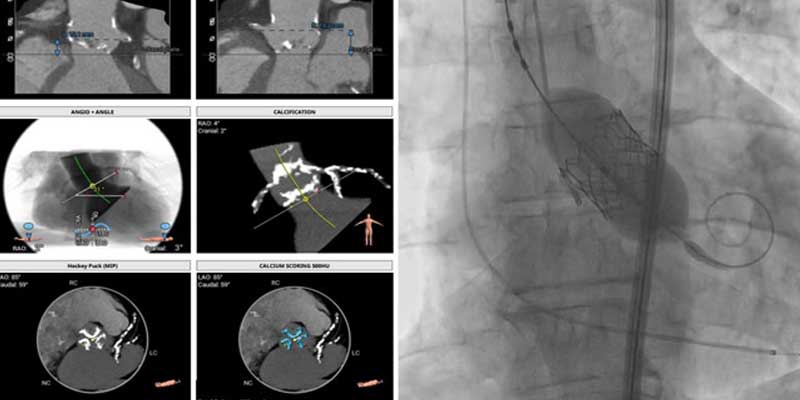

Treatment involves the use of advanced mechanical support devices such as Intra-Aortic Balloon Pump (IABP), Impella, or Extracorporeal Membrane Oxygenation (ECMO) during PCI. These devices support circulation, reduce cardiac workload, and enhance procedural safety while enabling complete and effective revascularization.